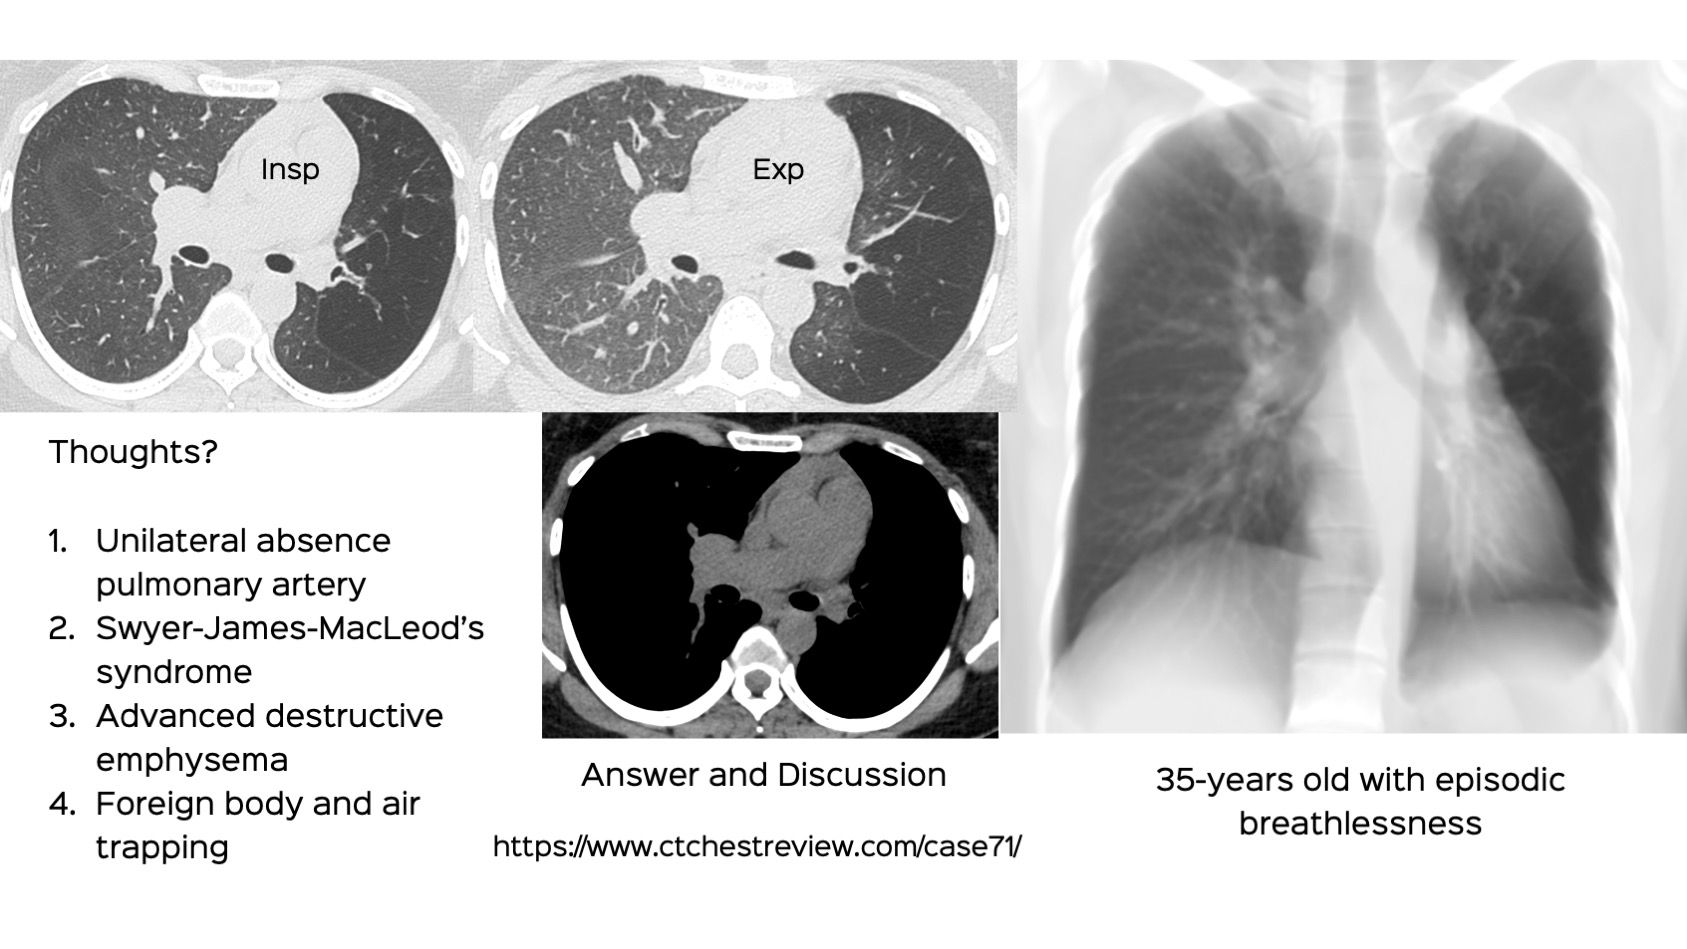

From www.ctchestreview.com

Case 71 Unilateral Lucent Lung Lung Field Lucency  Areas of diminished lung density are frequently identified both on routine chest radiographs and chest ct examinations. Decreased lung density on images can be described as pulmonary hyperlucency on conventional chest radiographs and. This relative overaeration may be due to subnormal blood perfusion,. The trapped air and mucus. Thin body habitus and poliomyelitis are important causes of hyperlucent lung fields. Lung Field Lucency.